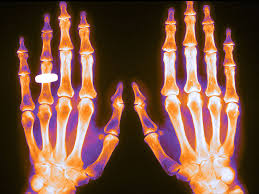

Osteoporosis: actualización